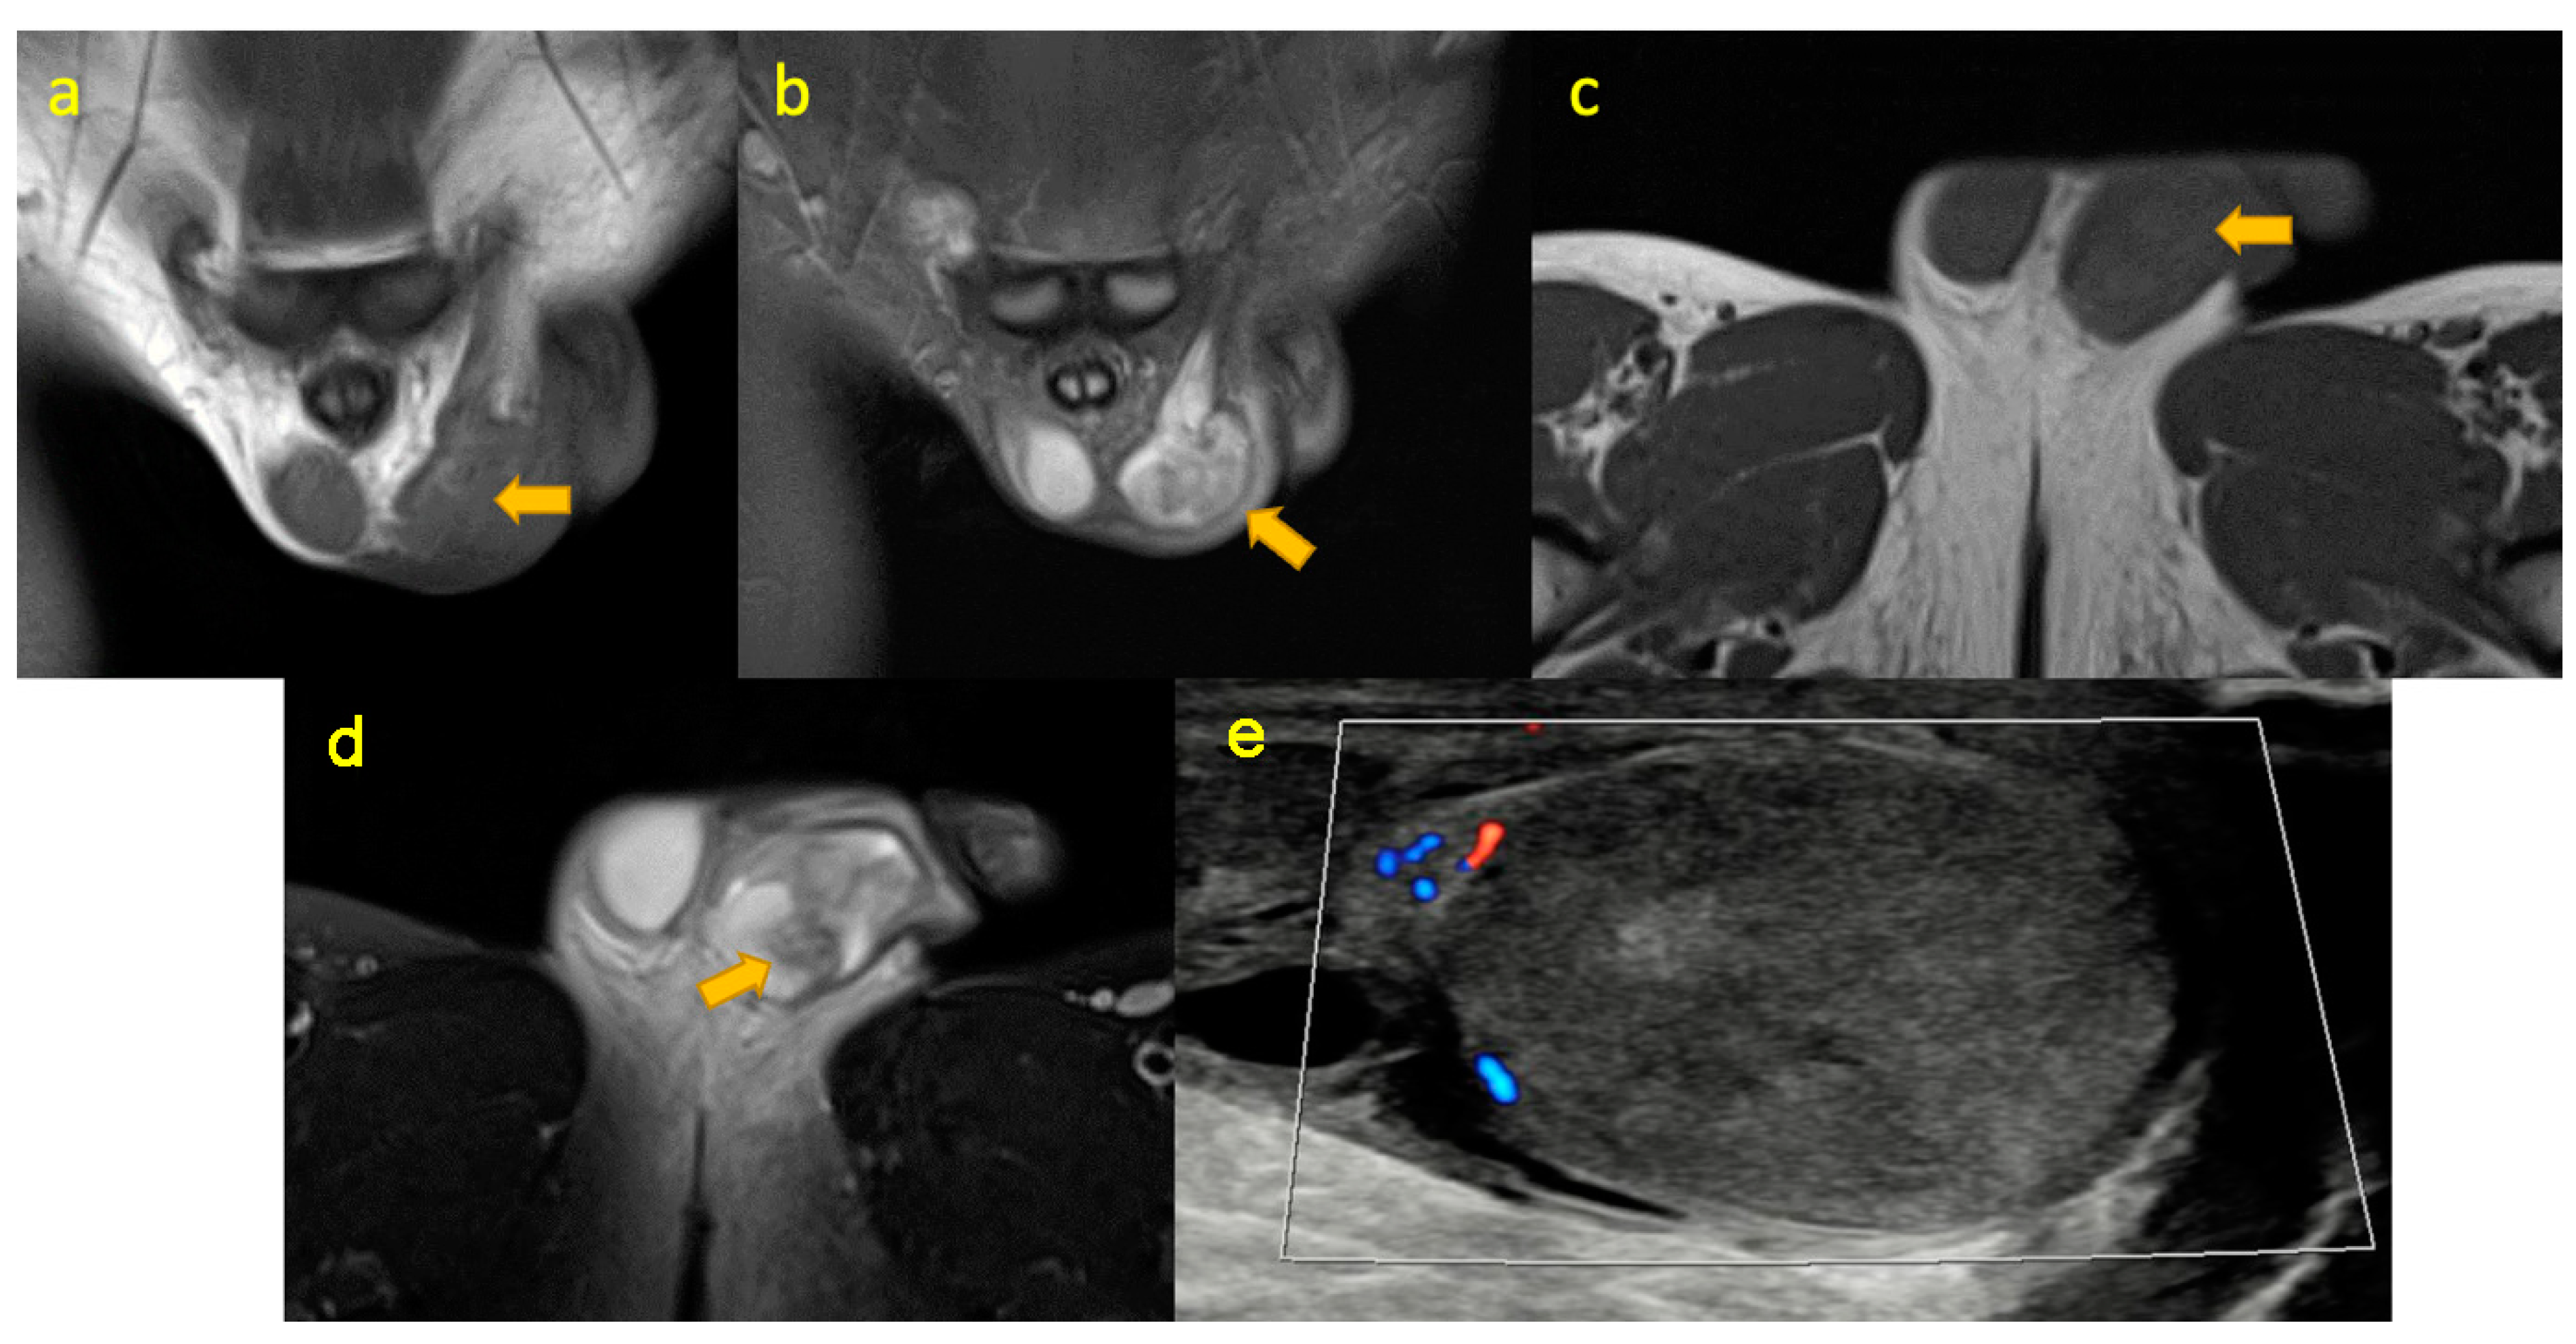

17. Testicular Torsion